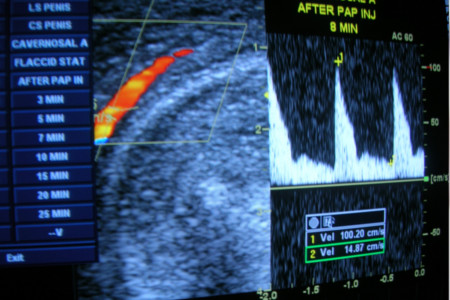

PENILE DOPPLER TEST : This is done in the scan room.Penile blood flow is checked with a Doppler probe. Vasodilator medicines are given orally or by an injection in to the penis and the blood flow increase is rechecked. Reduced peak systolic velocity identifies narrowing of penile artery.

Penile Blood Flow Checked by Doppler